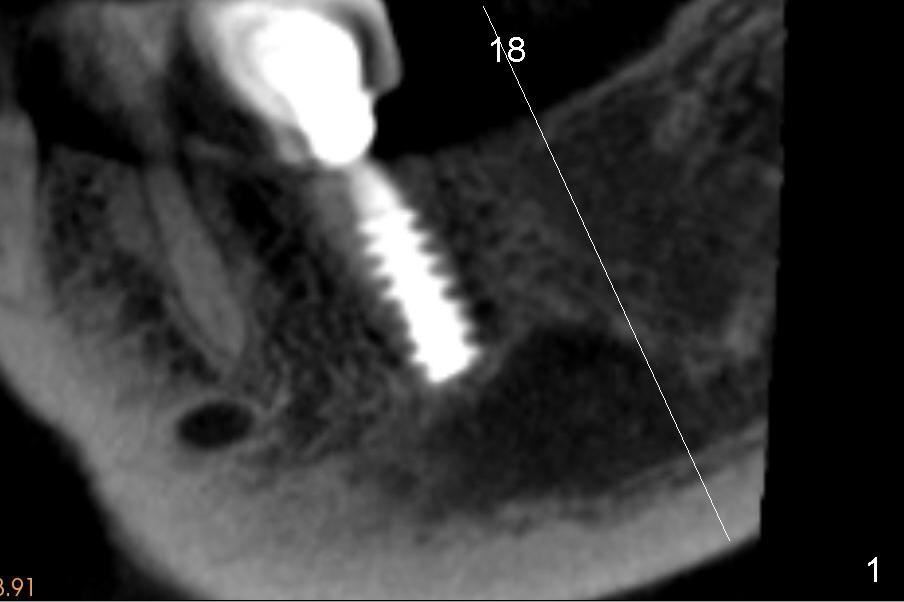

Abnormal anatomy of IAN is found (Fig.1' (sagittal section 200 µm): pink outline) at the site of #18 of a 56-year-old lady. There is an extra superior (coronal) bulging segment (Fig.1' red dashed line).

Let us make a coronal section through the white line in Fig.1.  The coronal section (Fig.2,2') confirms the superior extension (red line) of the nerve (pink circle).  The length of implant is limited. Since the ridge is wide, an extra wide implant is planned.  In addition, the top of the ridge is pointed (yellow dashed line).